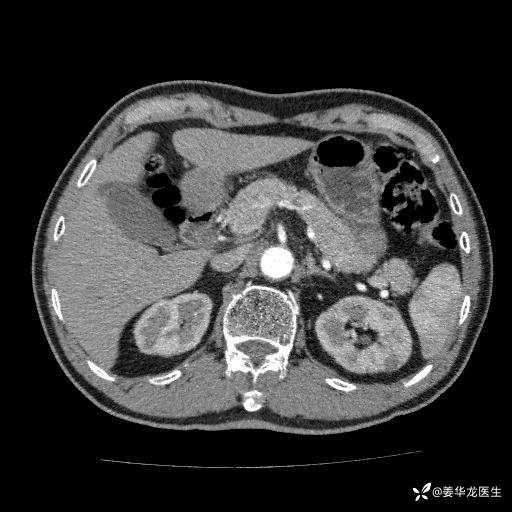

左肾中心型肾门部肿瘤39mm×34mm×36mm,右肾GFR25ml/min,部分切还是全切?

患者75岁老年男性,体重50kg,无高血压、肾病、糖尿病等基础病,检查发现左肾中心型肾门部肿瘤,右肾GFR只有25ml,无肉眼血尿,无镜下血尿。入院验血常规检查均正常,包括肾功能,肌酐102.7umol/L.

二、左肾肿瘤与左肾集合系、左肾动静脉关系密切,左肾部分切除术可行吗?成功率有多大?成功部分切后,肾功能还有多少?